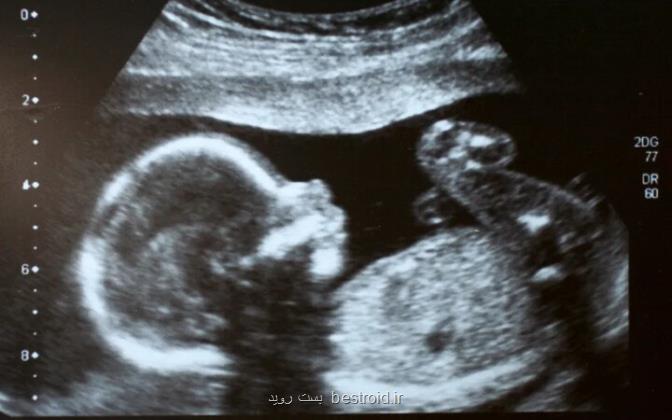

به گزارش بست روید، اولین نوزاد با ۳ والد در انگلیس متولد شده است. این نوزاد طی پژوهش محققان دانشگاه نیوکاسل و با استفاده از دی ان ای اهدایی از مادر ثانویه برای ترمیم یک صدمه ژنتیک متولد شد.

به گزارش بست روید به نقل از تلگراف، روش باروری مذکور به پزشکان اجازه داد تا میتوکندری صدمه دیده دی ان ای را با یک نمونه سالم از یک اهداکننده زن دیگر جایگزین کنند تا بدین سان از ابتلای کودک به بیماری های ارثی مانند تحلیل عضلانی اجتناب شود. بعد از این فرآیند تخمک های ترمیم شده با اسپرم بارور شدند و نطفه ها به وسیله یک فرآیند مشابه آی وی اف که درمان جایگزین میتوکندریایی(MRT) نام دارد، در بدن مادر قرار گرفتند. هرچند پزشکان هنوز تولد نوزادانی با این روش را اعلام نکرده اند اما درخواست روزنامه گاردین برپایه آزادی اطلاعات از سازمان لقاح و جنین شناسی انسان (HFEA) تایید شد و طبق اعلام آن سازمان، تعداد اندکی نوزاد با استفاده از روش انتقال میتوکندری متولد شده اند. هنوز از سلامت نوزادان خبری منتشر نشده است. البته نشریه پرس اسوسیشن در خبری دیگر اعلام نمود کمتر از ۵ نوزاد در انگلیس با کمک اهدای میتوکندریا تا ۲۰ آوریل متولد شده اند. اطلاعات دیگر برای شناسایی نشدن خانواده ها منتشر نشده است. هرچند این روش اولین بار در مرکز باروری نیوکاسل انجام شده اما در واقع اولین نوزاد متولد شده با کمک چنین فرایندی در مکزیک و در سال ۲۰۱۶ به دنیا آمده است. انگلیس تا پیش از ۲۰۱۷ میلادی اجازه انجام این فرآیند را نمی داد. در این میان محققان انگلیسی تلاش کردند تا روش مذکور را ارتقا دهند که به تولد اولین نوزاد با دی ان ای ۳ نفر منجر گردید. حدود ۹۹.۸ درصد دی ان ای نوزاد به مادر و پدر وی و بخش اندکی از آن به اهداکننده متعلق می باشد.